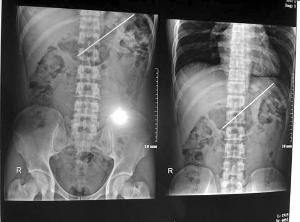

檢查顯示胃里有一狹長異物

取出來的燒烤釬子長18厘米醫(yī)院供圖

醫(yī)生先是給他安排了腹部平片檢查,片子上顯示,他的胃部有一狹長異物,已經(jīng)到達(dá)了胃底。“因為李樂已經(jīng)吞了釬子一個多月了,而且釬子太長,無法從幽門排出,為了防止惡化,必須馬上進(jìn)行手術(shù)。”八一醫(yī)院消化內(nèi)科主任文衛(wèi)介紹。